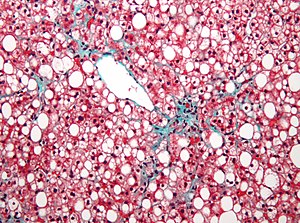

| Micrograph showing a fatty liver (macrovesicular steatosis), as seen in non-alcoholic fatty liver disease. Trichrome stain. | |

Fatty change represents the intracytoplasmatic accumulation of triglycerides (neutral fats). At the beginning, the hepatocytes present small fat vacuoles (liposomes) around the nucleus (microvesicular fatty change). In this stage, liver cells are filled with multiple fat droplets that do not displace the centrally located nucleus. In the late stages, the size of the vacuoles increases, pushing the nucleus to the periphery of the cell, giving characteristic signet ring appearance (macrovesicular fatty change). These vesicles are well-delineated and optically "empty" because fats dissolve during tissue processing. Large vacuoles may coalesce and produce fatty cysts, which are irreversible lesions. Macrovesicular steatosis is the most common form and is typically associated with alcohol, diabetes, obesity, and corticosteroids. Acute fatty liver of pregnancy and Reye's syndrome are examples of severe liver disease caused by microvesicular fatty change.[18] The diagnosis of steatosis is made when fat in the liver exceeds 5–10% by weight.[11][19][20]